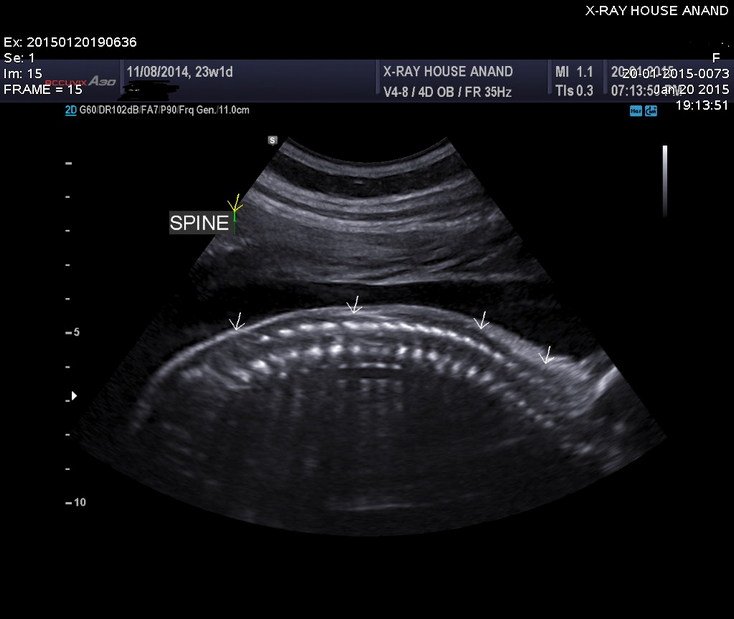

2D Sonography-Foetal Spine